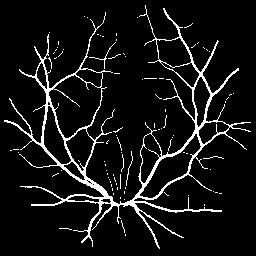

FIVES dataset [14] consists of 800 high-quality multi-disease fundus images and annotated segmentation masks. We partition this dataset into 70% for training (560 images), 10% for validation, and 20% for testing. Similar to ACDC, we use 5% (28 images) and 10% (56 images) of the 560 training images as labeled data to simulate low-data availability, treating the remaining data as unlabeled.

Synthetic Data: For our experiments, high-fidelity synthetic images are generated using StyleGAN2-ADA [16] as described in Section 3.1.2. The model is trained exclusively on the limited percentage of real labeled data available for each dataset (e.g., 5% or 10%). For instance, when using 10% labeled data (136 images for ACDC or 56 for FIVES), StyleGAN2-ADA is trained solely on these specific images. Figure 3 shows random synthetic samples generated for both ACDC and FIVES datasets at 5% and 10% labeled data splits.

Quantitative Results: Table 2 shows that SRA-Seg achieves the best DICE scores among all methods using synthetic unlabeled data in both 5% and 10% splits, even outperforming methods using real unlabeled data.

Qualitative Results: Figure 7 provides qualitative segmentation results on the FIVES dataset. Consistent with our quantitative analysis, these visualizations highlight SRA-Seg’s superior performance in accurately segmenting various anatomical structures compared to other approaches.